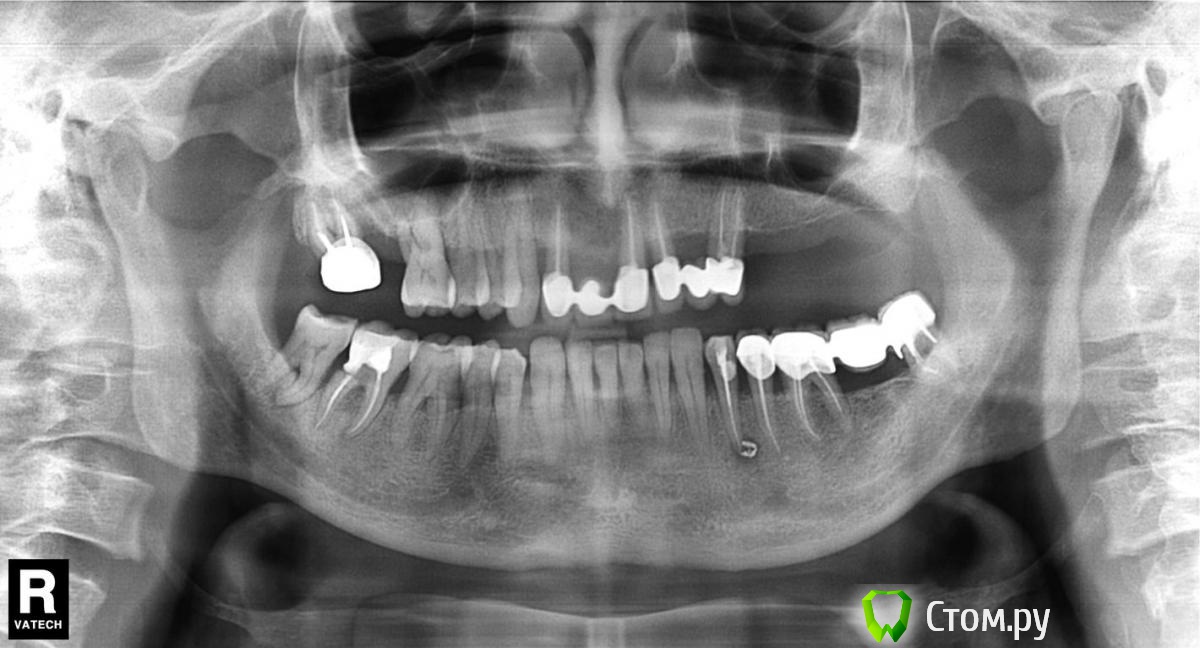

wladdX Опубликовано 11 февраля, 2014 Поделиться Опубликовано 11 февраля, 2014 (изменено) Прошу прощения за вторжение в чужую тему (администратор, поправьте), но ситуация похожа. Т.е. помимо синус-лифтинга надо увеличить ширину альвеолярного отростка. Предполагаю поступить примерно, как продемонстрировал Mane выше. Но может подойдёт "метод полужёстких каркасов? Кстати септа в пазухе замысловатая. По поводу остальных сегментов и прочих проблем - пациент на них не настроен, интересует его только зона 25,26,27 Изменено 11 февраля, 2014 пользователем wladdX Ссылка на комментарий